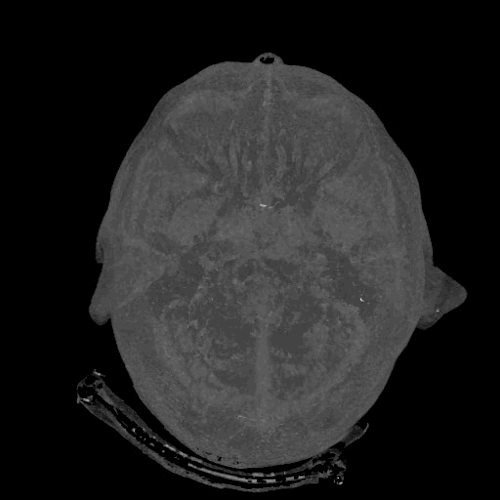

9. Chất lỏng chảy ra khỏi mũi có thể là từ não

![]() |

| Ảnh: BrightSide |

Chất lỏng rò rỉ qua mũi có thể là chất lỏng trong não. Chất lỏng này nằm xung quanh não và được giữ trong một màng đặc biệt. Đôi khi chất này có thể rò rỉ qua mũi với lượng nhỏ dưới dạng chất lỏng trong suốt.